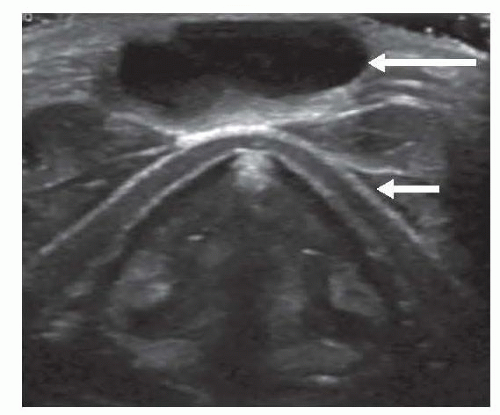

Ultrasonography of the neck and thyroid to evaluate the swelling and confirm a normal thyroid is present (FIG 4).

In the absence of a thyroid gland, a thyroglossal duct cyst (TGDC) may contain the only functioning thyroid tissue.

Nuclear imaging in the form of radioactive iodine scan can be used if there is doubt regarding normal functioning thyroid.